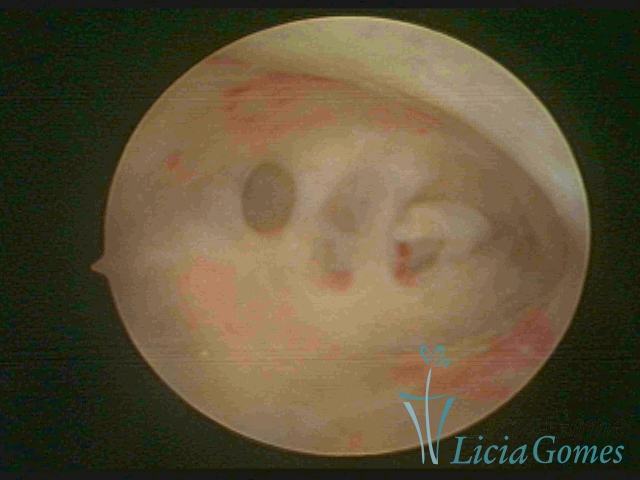

FIBROUS SYNECHIA

Uterine synechiae are scars (adherence) between the surface of the uterine walls, which may occur after the surgical procedure, uterine curettage, or after an inflammatory process in the uterine cavity (endometritis), which may lead to menstrual changes, infertility and obstetric complication such as abortion and premature birth.

• SINÉQUIA TIPO FIBROMUSCULAR